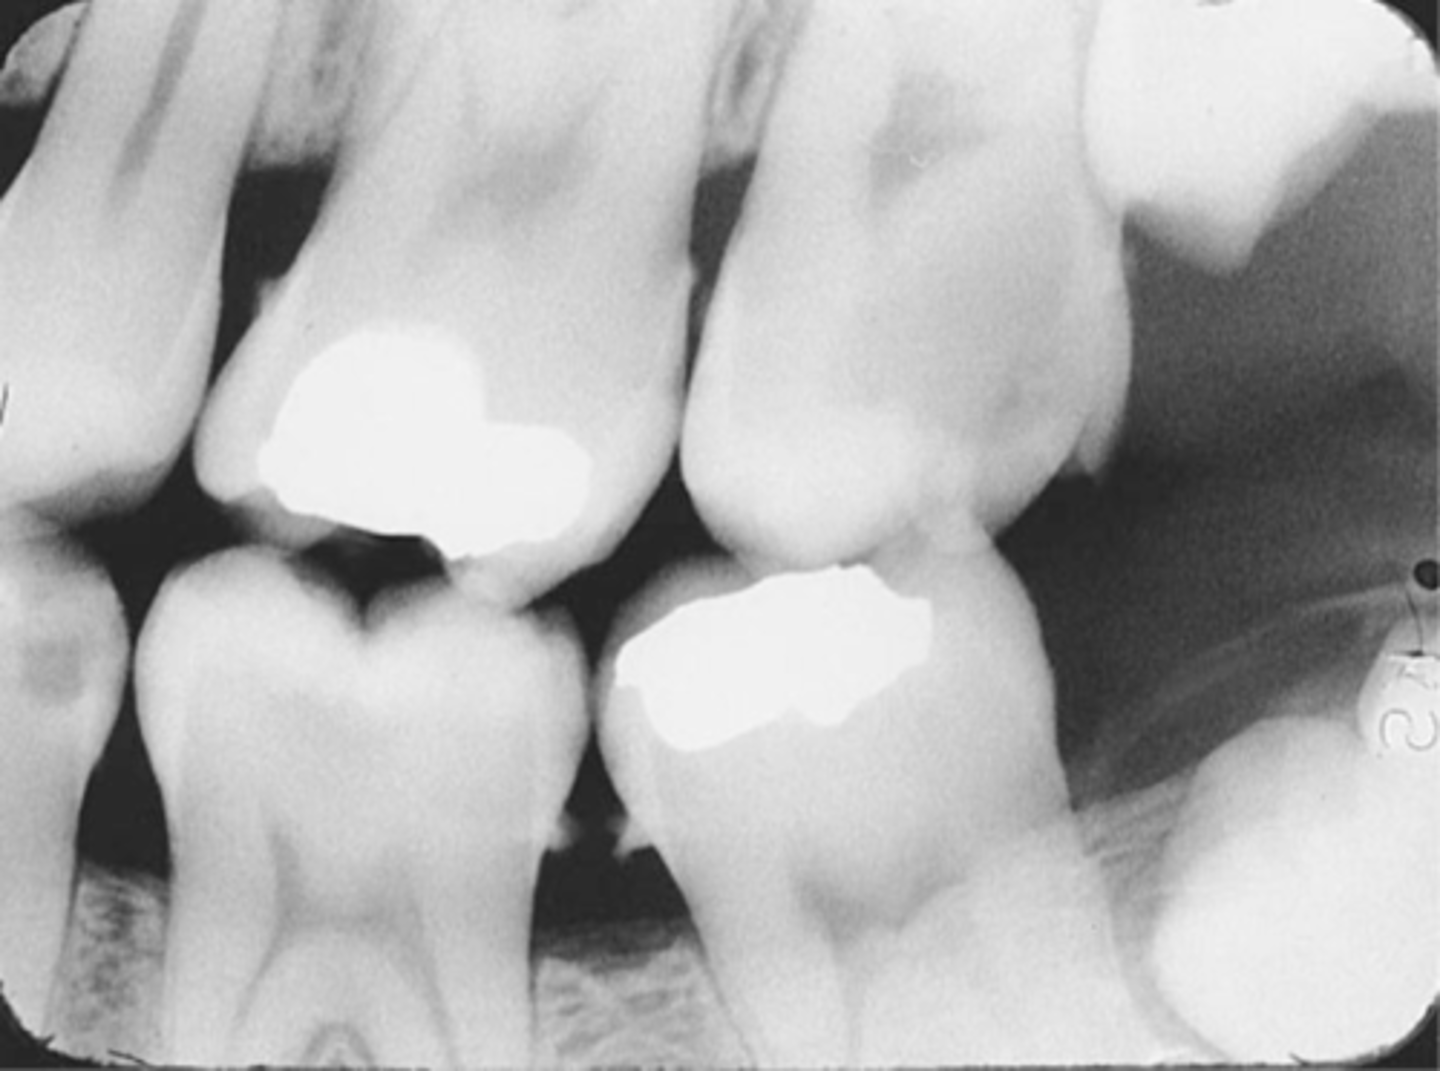

Premolar Bite-Wing

-Bite-Wing must be positioned so that the resulting image shows both max and mand premolars and the distal contact of the canines.

-Receptor must be positioned so that the front edge of the receptor is aligned with the midline of the mand. canine.

Molar Bite-Wing

-Bite-wing must be positioned so that the resluting image shows both max and mand molars, and centered over the mand 2nd molar.

-Receptor must be positioned so that the front edge of the receptor is aligned with the midline of the mand. 2nd premolar